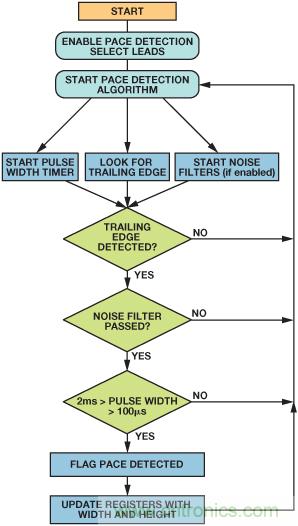

起搏器算法的簡化流程圖如圖9所示。

圖9. 起搏算法的流程圖

器件的前端包含一種數(shù)字起搏器偽像檢測算法,可以檢測到寬度范圍為100 μs至2 ms、幅度范圍為400 μV至1000 mV的起搏偽像——符合上述AAMI和IEC標(biāo)準(zhǔn)。根據(jù)測試結(jié)果和醫(yī)師意見,這些限制要比醫(yī)用標(biāo)準(zhǔn)寬松許多。

起搏檢測算法在四根可能的導(dǎo)聯(lián)線(I、II、III或aVF)中的三根上運(yùn)行三個(gè)數(shù)字算法實(shí)例。在高頻心電圖數(shù)據(jù)上運(yùn)行,與內(nèi)部抽取和濾波并行運(yùn)行。該算法設(shè)計(jì)用于檢測并測量寬度范圍為100 μs至2 ms、幅度范圍為400 μV至1000 mV的起搏偽像,返回一個(gè)標(biāo)志,用以表示是在一根還是多根導(dǎo)聯(lián)線上檢測到起搏信號,同時(shí)返回檢測到的信號的高度和寬度。對于希望運(yùn)行自己的數(shù)字起搏算法的用戶,ADAS1000提供了一個(gè)高速起搏接口,可以快速的數(shù)據(jù)速率(128 kHz)提供心電圖數(shù)據(jù),與此同時(shí),標(biāo)準(zhǔn)接口上經(jīng)過濾波和抽取的心電數(shù)據(jù)保持不變。

這種起搏偽像系統(tǒng)是由一個(gè)工程師和起搏專家團(tuán)隊(duì)與起搏行業(yè)共同研發(fā)的。這種合作帶來了一種同步三矢量起搏偽像檢測系統(tǒng),該系統(tǒng)可以檢測起搏偽像,盡管電氣噪聲顯著大于偽像。三個(gè)起搏算法實(shí)例中的每個(gè)實(shí)例都可以編程以檢測不同導(dǎo)聯(lián)線(I、II、II或aVF)上的起搏信號。該系統(tǒng)的閾值水平可編程,因而可以針對實(shí)際的脈沖寬度和高度檢測范圍進(jìn)行定制,同時(shí)還配置內(nèi)部數(shù)字濾波器,以便抑制心跳、噪聲和分鐘通氣量脈沖。當(dāng)證實(shí)起搏信號的單個(gè)實(shí)例中存在起搏信號時(shí),器件會(huì)輸出一個(gè)標(biāo)志,因而,用戶可以在心電圖上標(biāo)記或識別出起搏信號。